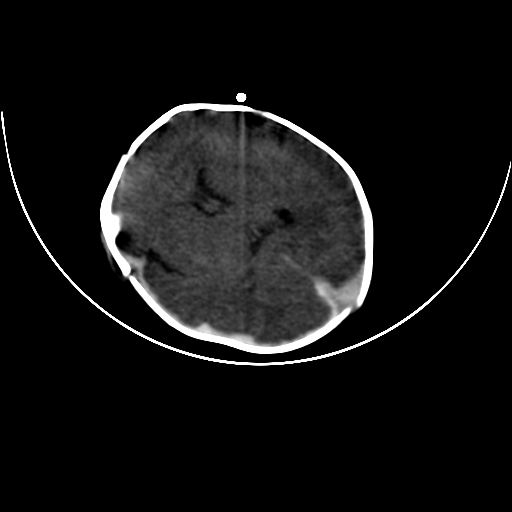

双侧硬膜下血肿并蛛网膜下腔出血。

双侧硬膜下血肿并蛛网膜下腔出血

hie 蛛网膜下腔出血,硬膜下血肿。

hie;双侧硬膜下血肿并蛛网膜下腔出血

双侧硬膜下血肿并蛛网膜下腔出血,考虑维生素k缺乏引起.

较大范围出血,应考虑维生素k缺乏引起,结合临床吧。

好像脑实质没有明显低密度影,各位大侠怎么支持hie呢?